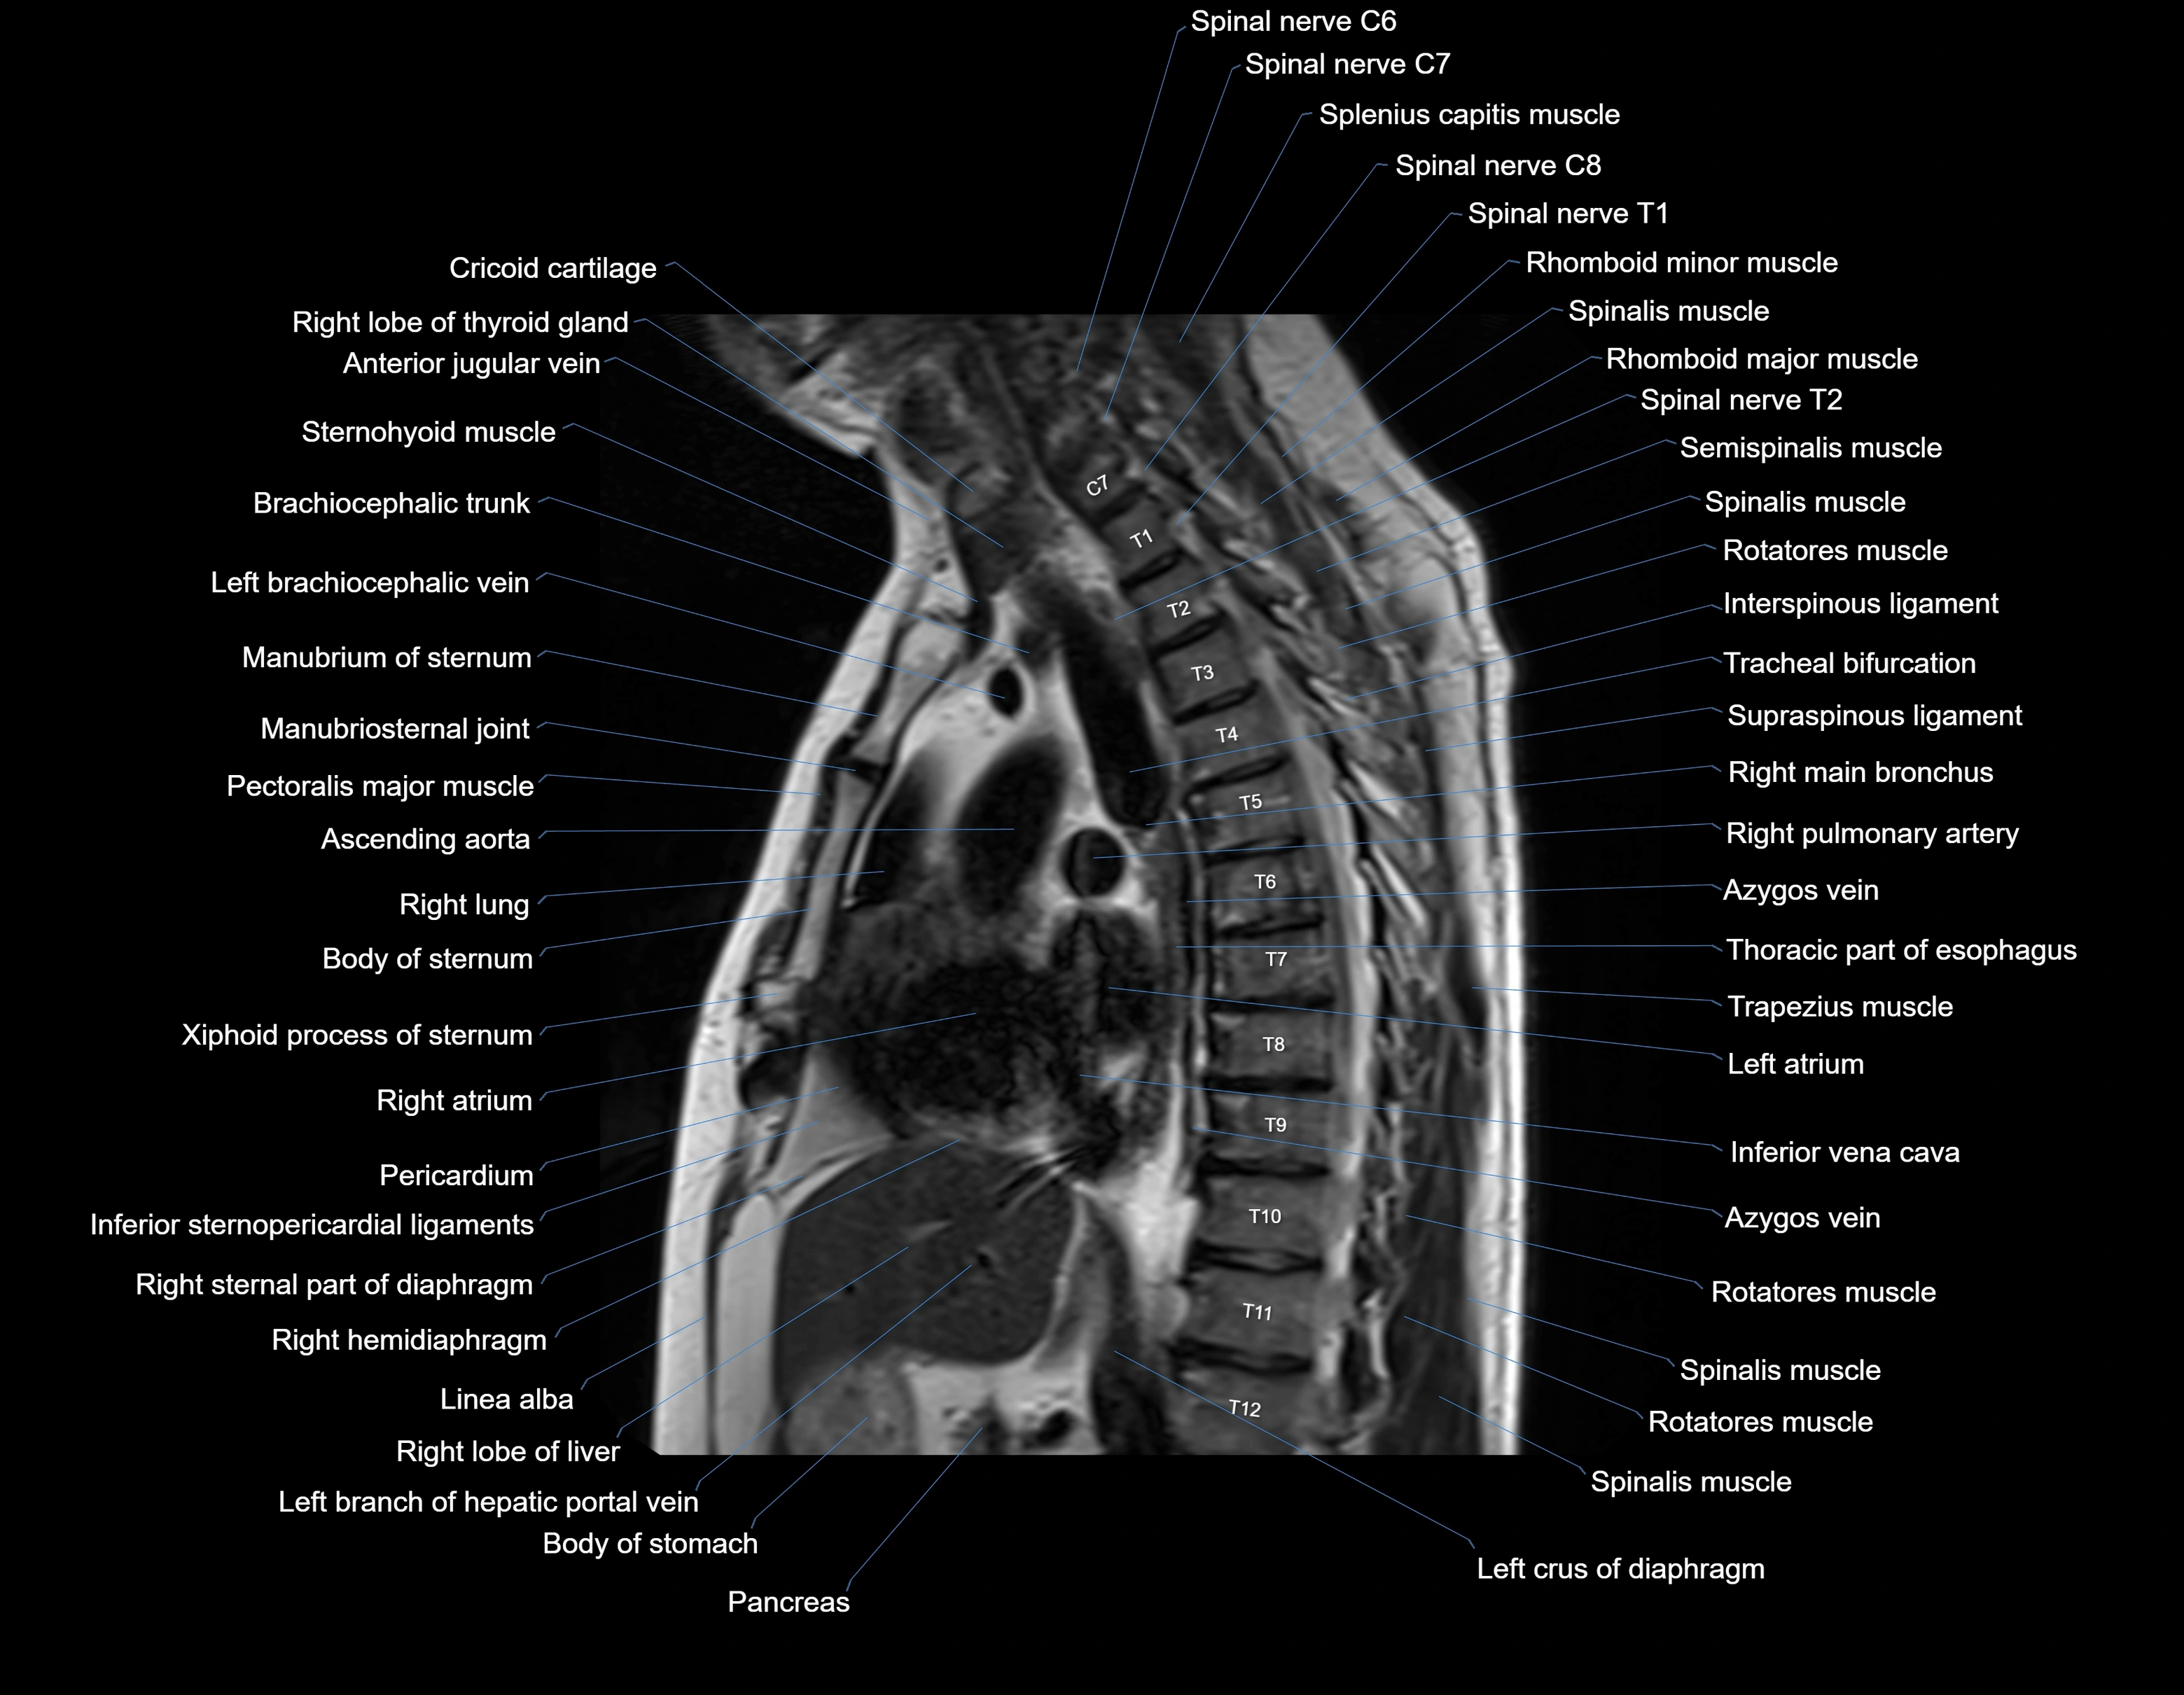

MRI images